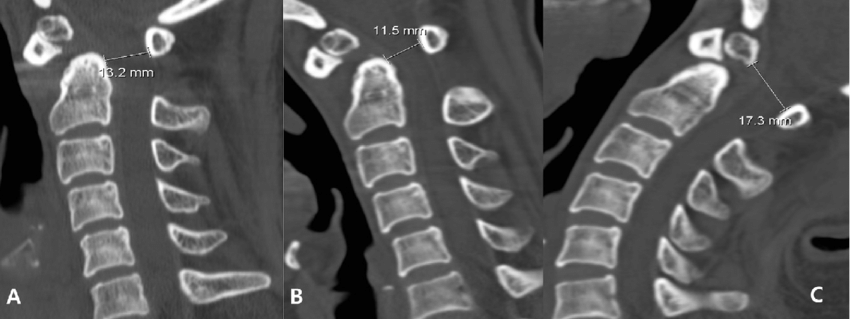

2.CT-Scan:

It is useful for cross-sectional imaging of the spine and increased image detail of the spinal cord,nerves and discs are investigated.